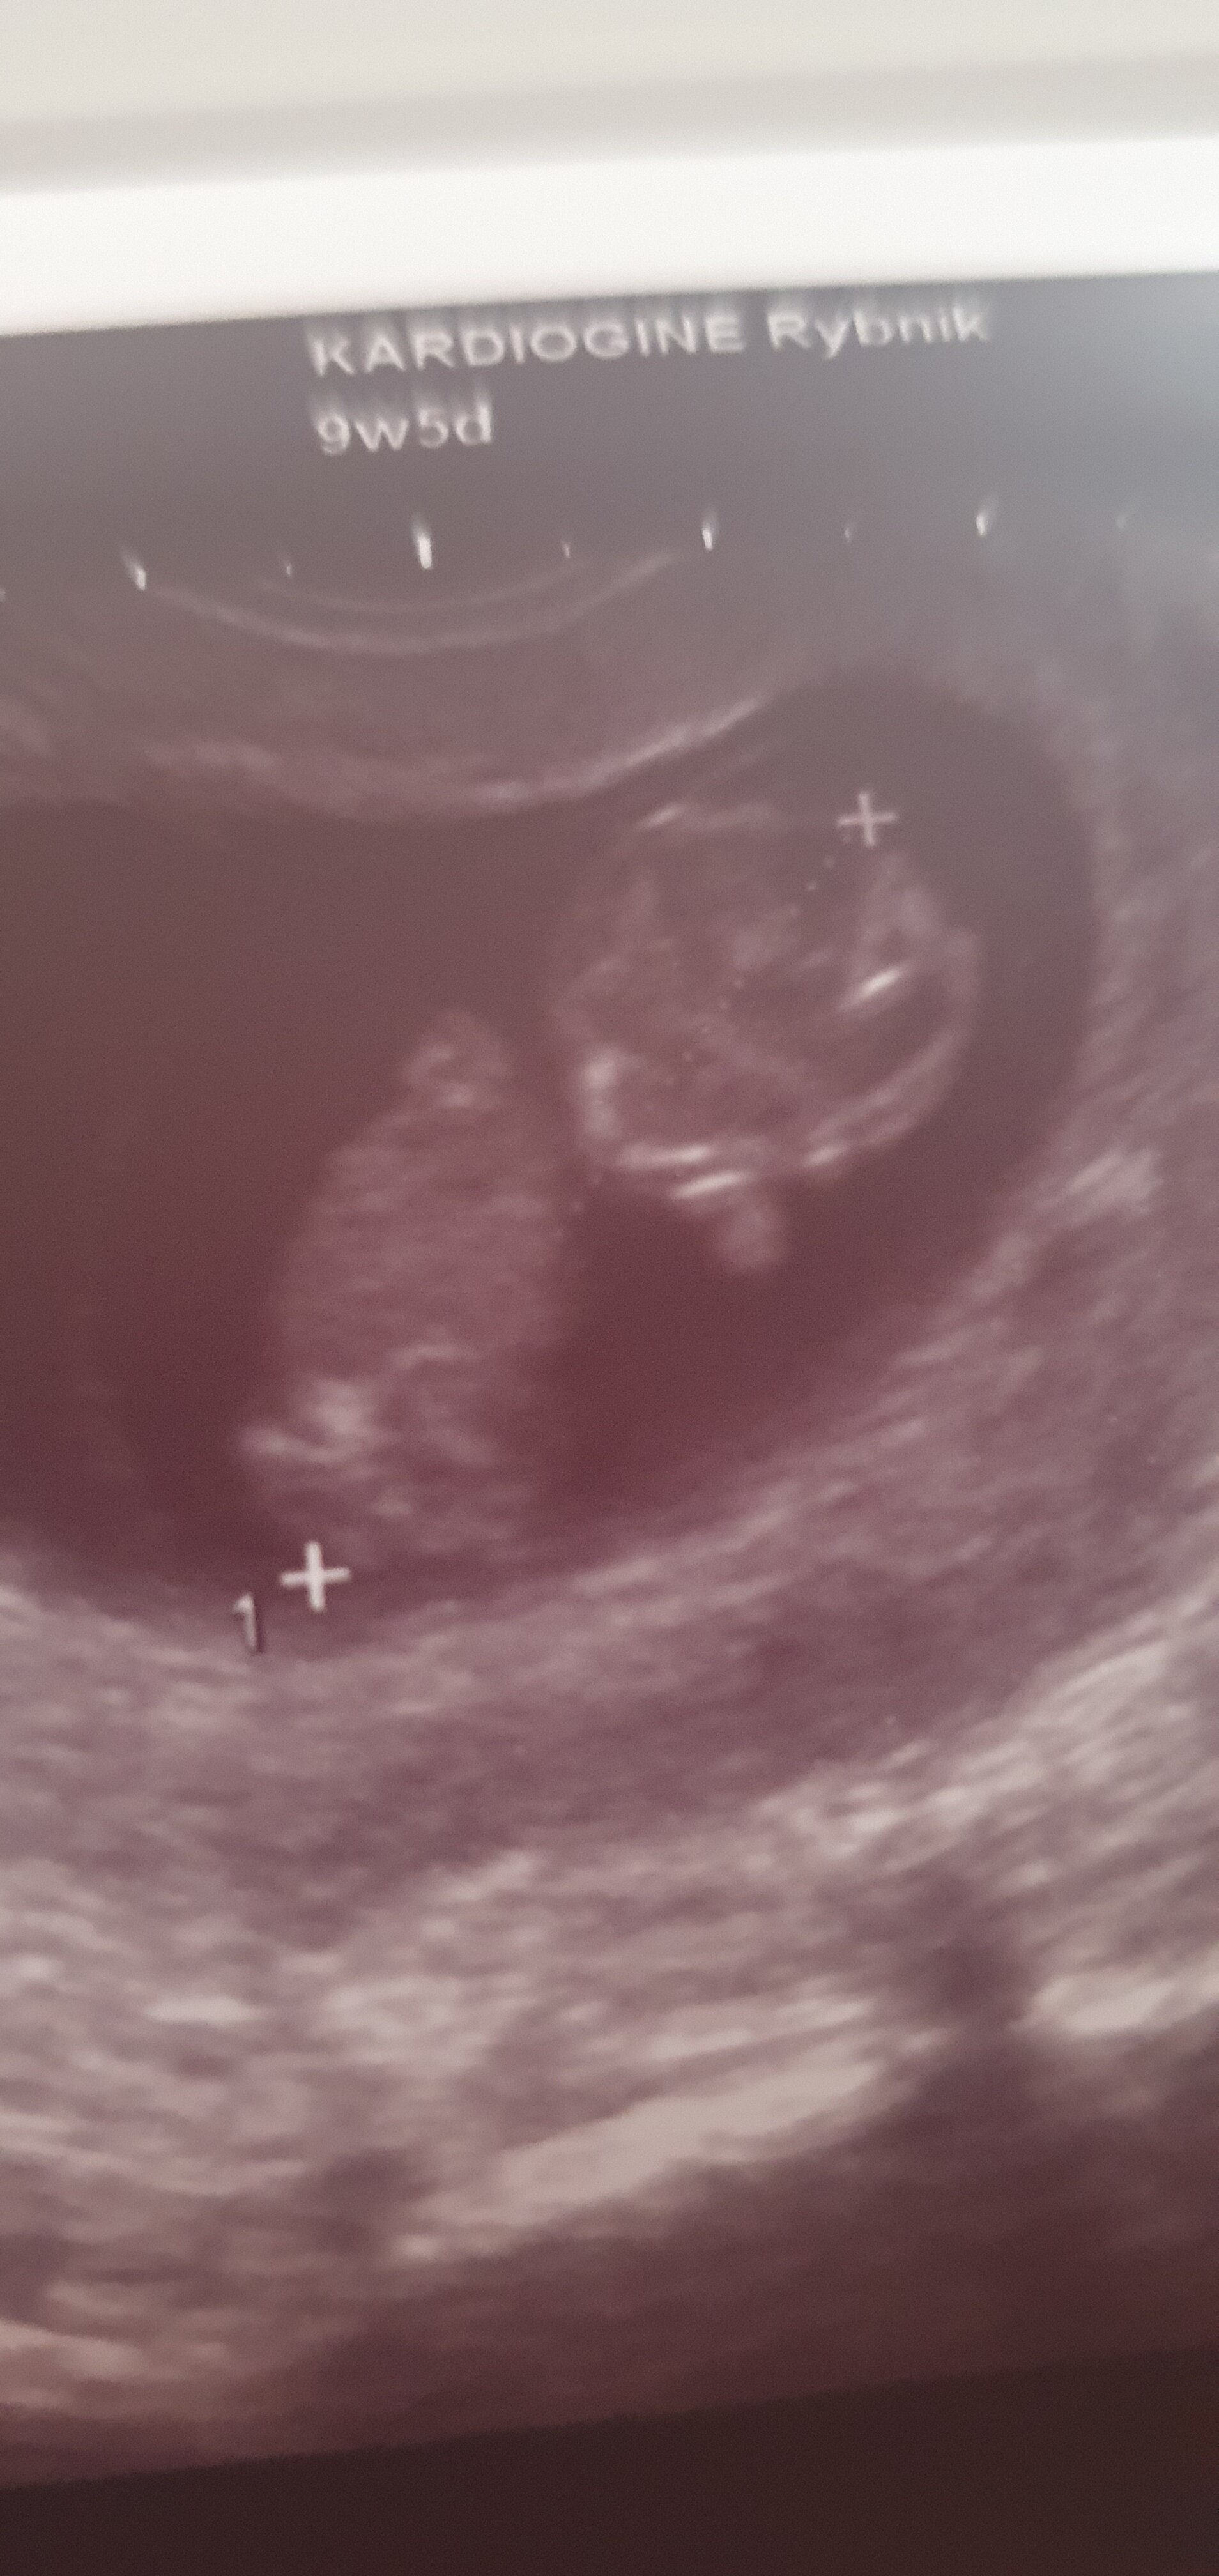

Ja miałam 2 wizyty w 8 i 10 to i 2 razy mi puściła na 1 sekundę ale to dlatego ze jestem po poronieniu zatrzymanym i pierwsze moje pytanie jest zawsze czy żyje. Więc żeby mnie uspokoić to mi puściła. Moja lekarka mi nawet ciśnienia nie mierzy bo przed USG mam takie nerwy ciśnienie 140 ale mierze w domu i ok jestHej, jak często puszczaja Wam bicie serduszka? Ja jestem w 11 tygodniu ciąży i już dwa razy. A czytałam że USG dopplerowskie nie jest za dobre w tak wczesnej ciąży

Ja nie miałam jeszcze puszczanego.Hej, jak często puszczaja Wam bicie serduszka? Ja jestem w 11 tygodniu ciąży i już dwa razy. A czytałam że USG dopplerowskie nie jest za dobre w tak wczesnej ciąży